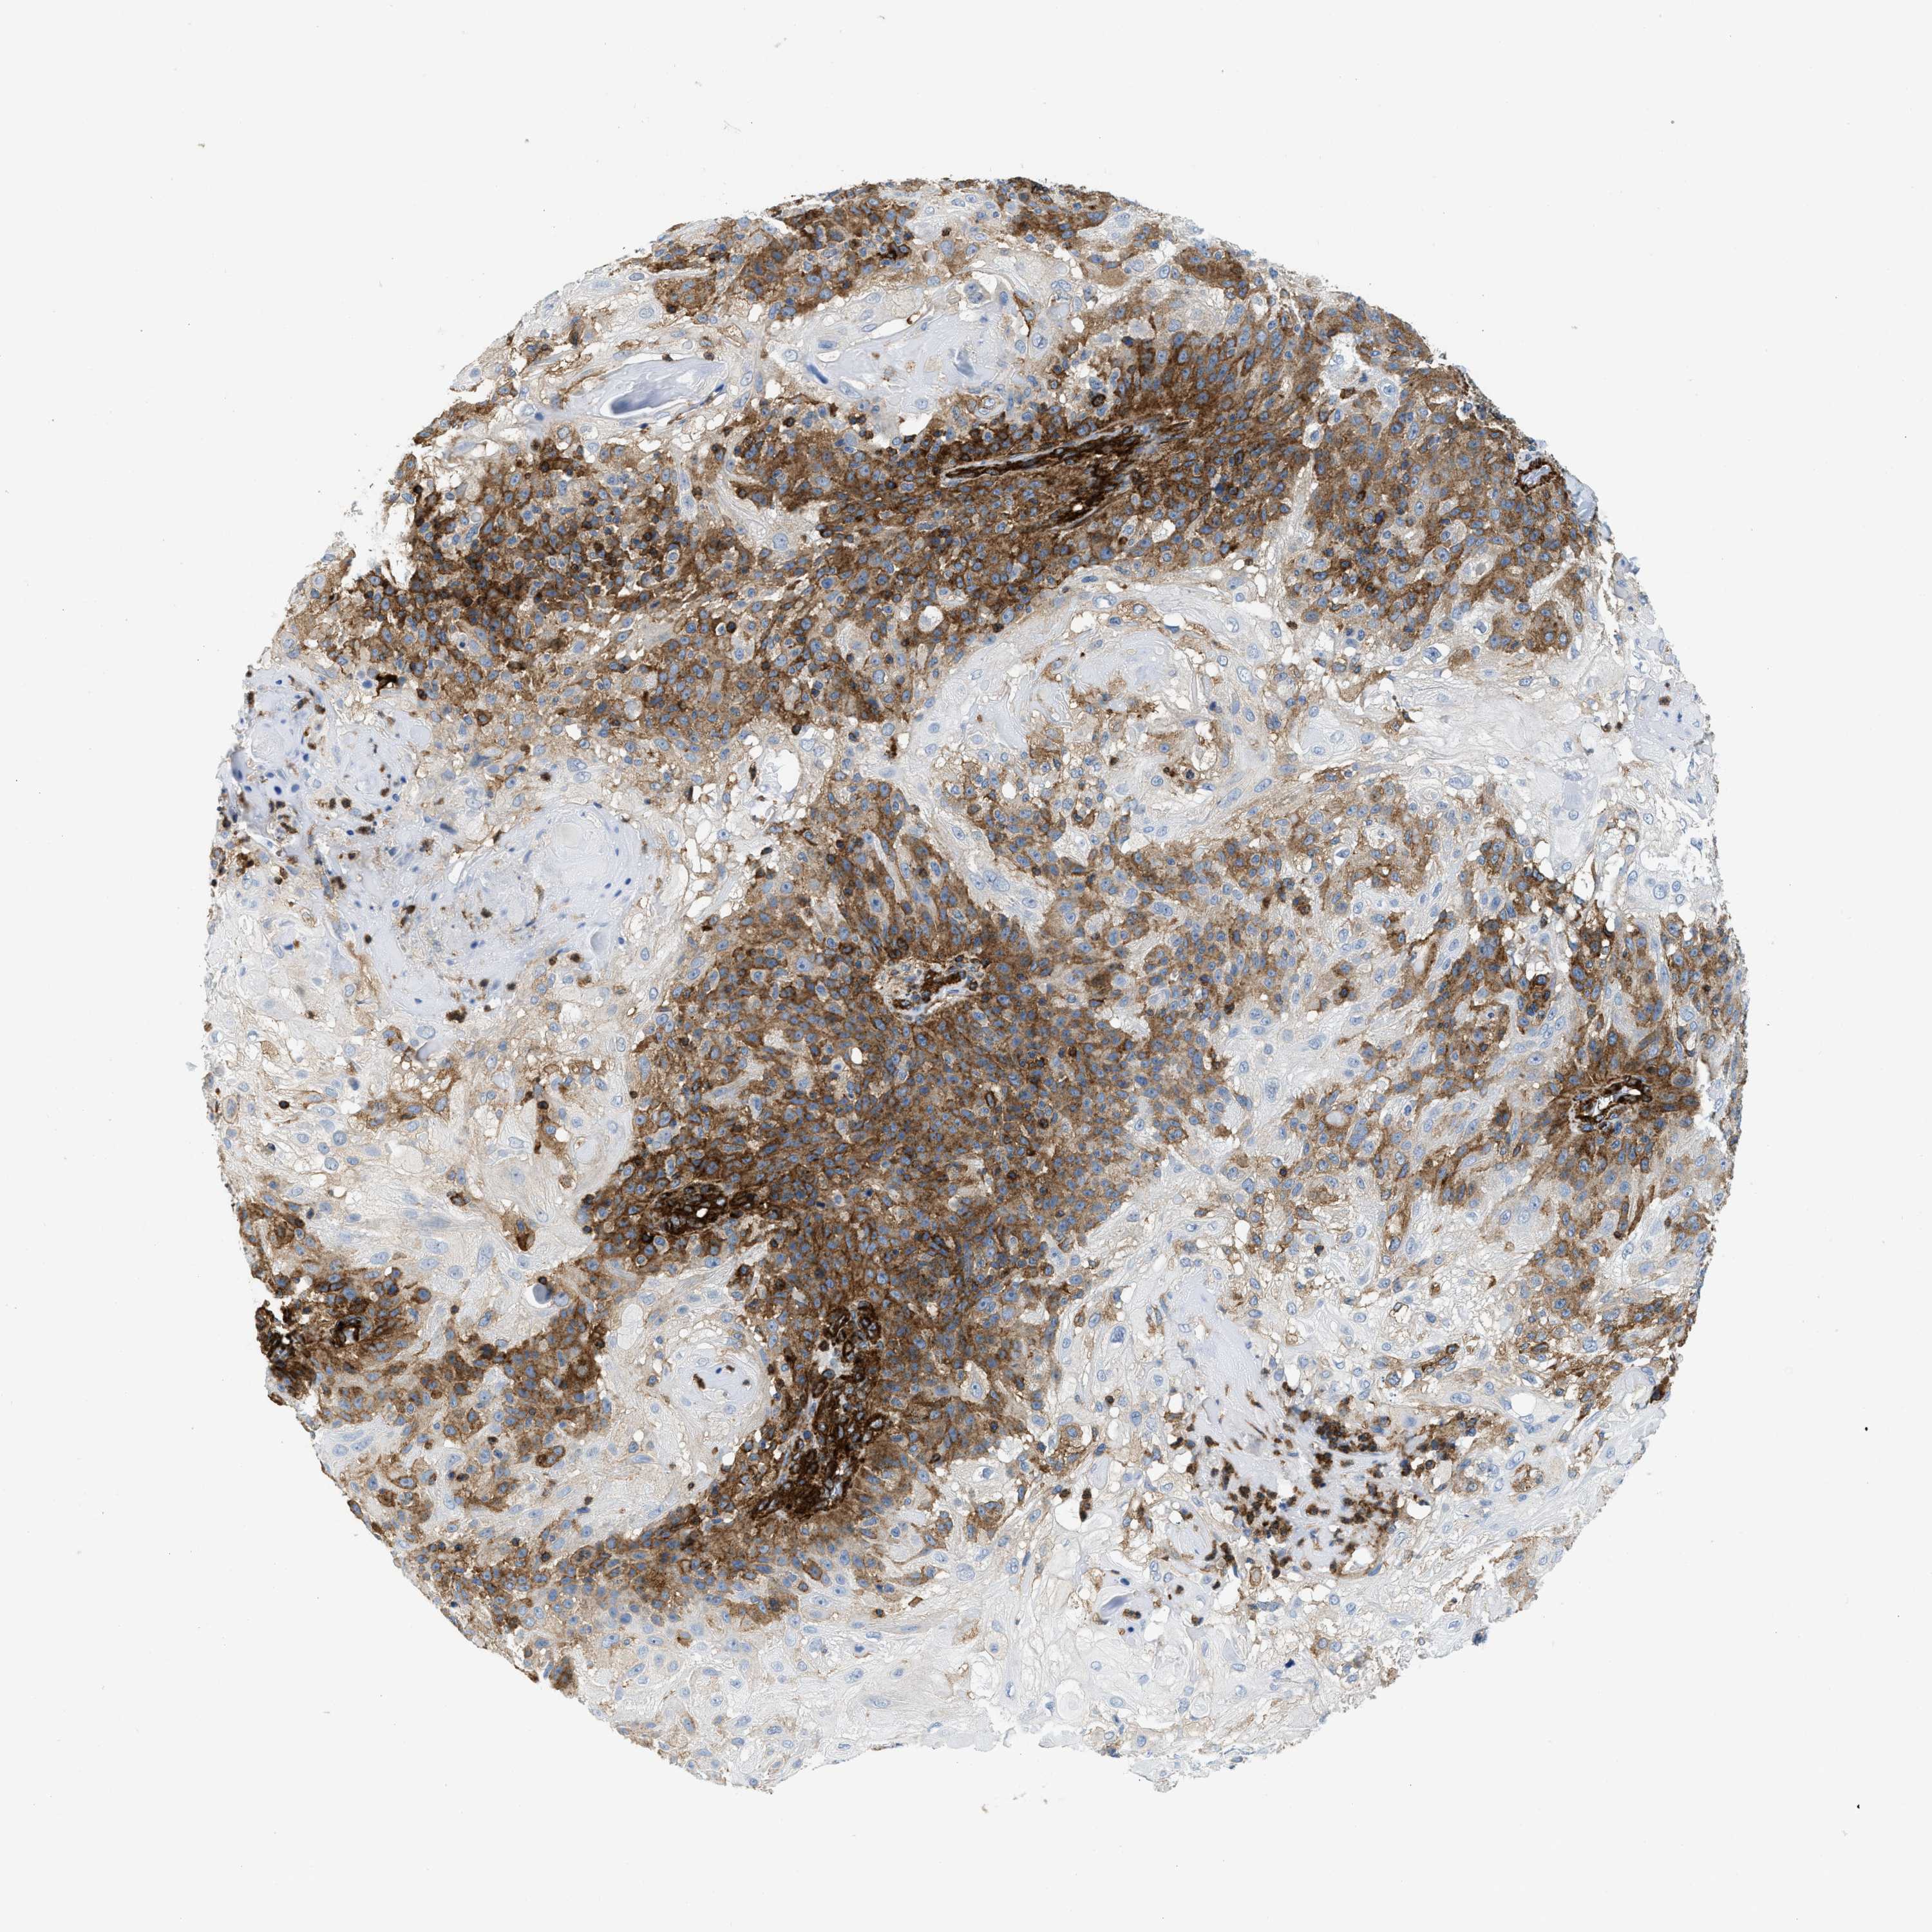

SKIN CANCER - Protein expressioni

A mouse-over function shows sample information and annotation data. Click on an image to view it in a full screen mode. Samples can be filtered based on level of antibody staining by selecting one or several of the following categories: high, medium, low and not detected. The assay and annotation is described here.

Antibody stainingi

Antibody staining in the annotated cell types in the current human tissue is reported as not detected, low, medium, or high, based on conventional immunohistochemistry profiling in selected tissues. This score is based on the combination of the staining intensity and fraction of stained cells.

Each image is clickable and will lead to virtual microscopy that enables deeper exploration of all samples and also displays staining intensity scores, fraction scores and subcellular localization as well as patient and tissue information for each sample.

Antibody HPA013606

Antibody HPA017964

Antibody CAB015334

Antibody CAB016402

Staining

High

Medium

Low

Not detected

Intensity

Strong

Moderate

Weak

Negative

Quantity

>75%

75%-25%

<25%

None

Location

Nuclear

Cytoplasmic/membranous

Cytoplasmic/membranous,nuclear

Squamous cell carcinoma in situ, NOS

Squamous cell carcinoma, NOS

Squamous cell carcinoma, metastatic, NOS

Basal cell carcinoma

Adnexal tumor, benign